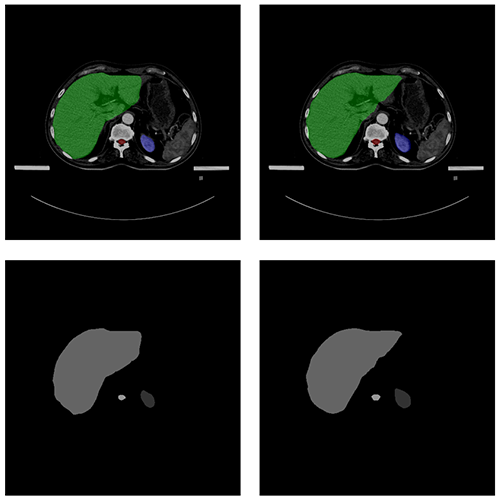

自動勾畫效果

AUTOMATIC CONTOURING

原圖

預測圖